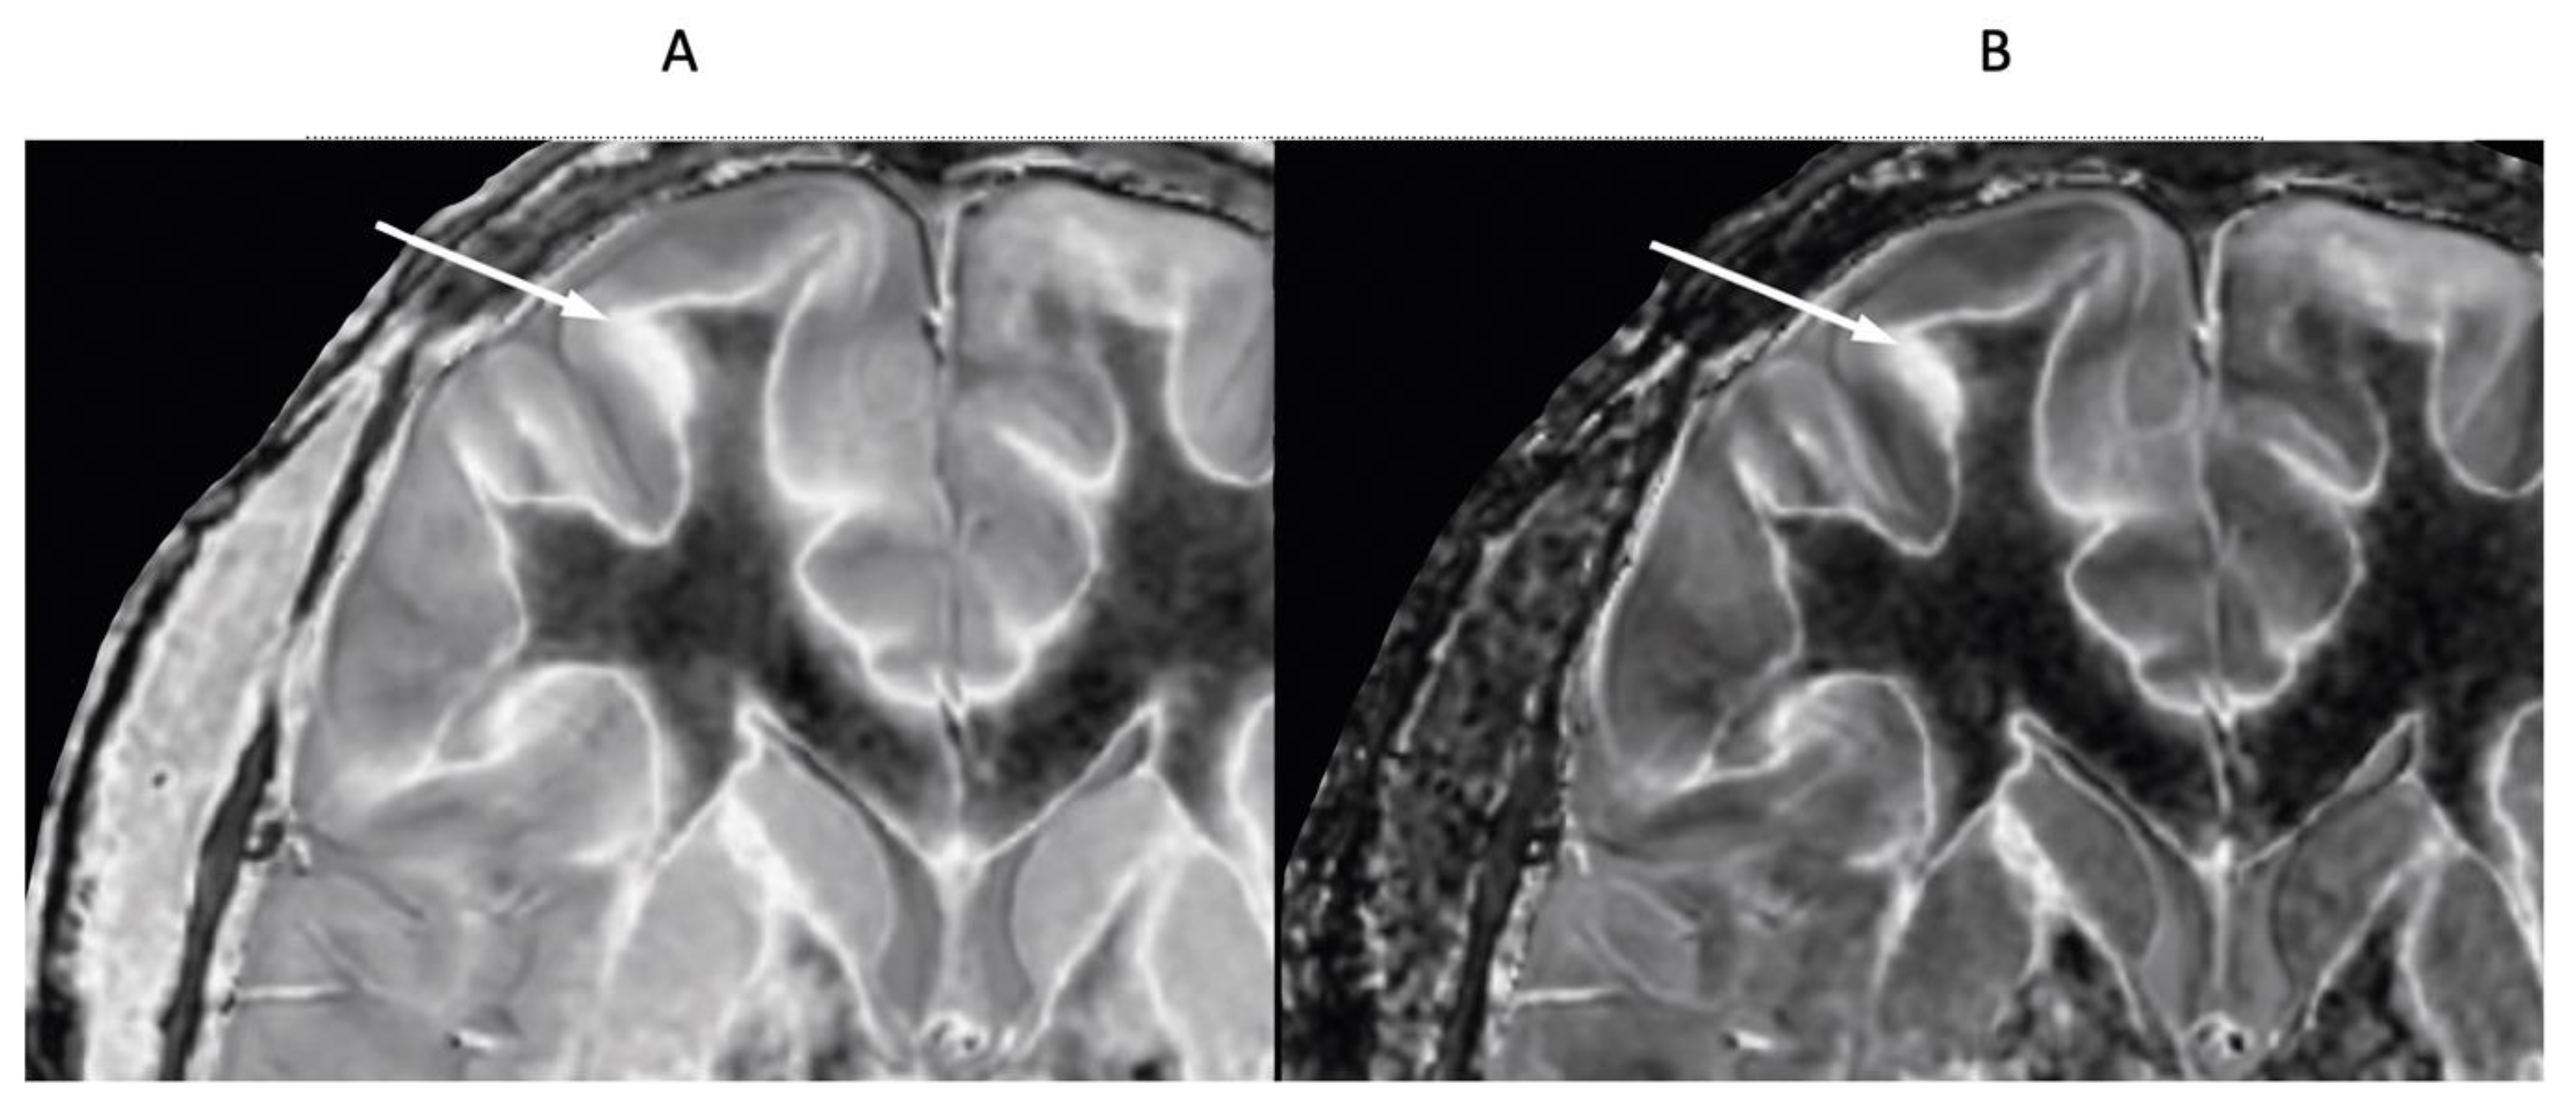

- Ultra-high contrast MRI using bipolar filters (BLAIRs) can show abnormalities with very high contrast where little or no change from normal is seen with common conventional state-of-the-art sequences.

- The abnormalities shown with ultra-high contrast are due to small changes in tissue properties such as T1 and T2 in disease. This is complementary to existing sequences which show abnormalities due to larger changes in T1 and T2 in disease.

- At boundaries between tissues and fluids on ultra-high contrast images there is frequently an increase in contrast and an increase in the spatial resolution of that contrast.

- Extensive abnormalities were seen in mild traumatic brain injury, multiple sclerosis and white matter associated with cerebral tumours in the absence of changes in T2-weighted spin echo or T2-FLAIR images.